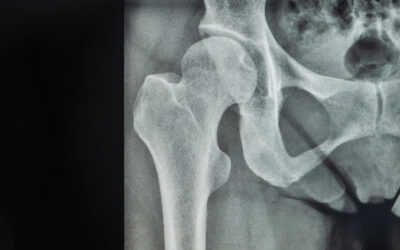

Hip Pain – Strategies to Address Your Osteoarthritis

Hip pain is a common concern, especially as we age, and one of the leading causes is osteoarthritis. Osteoarthritis, a degenerative joint disease, affects various joints in the body, with the hips...